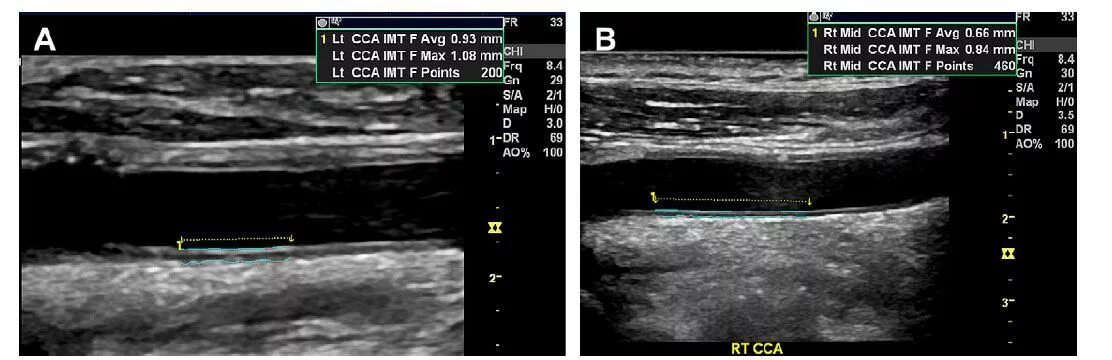

Threshold imt